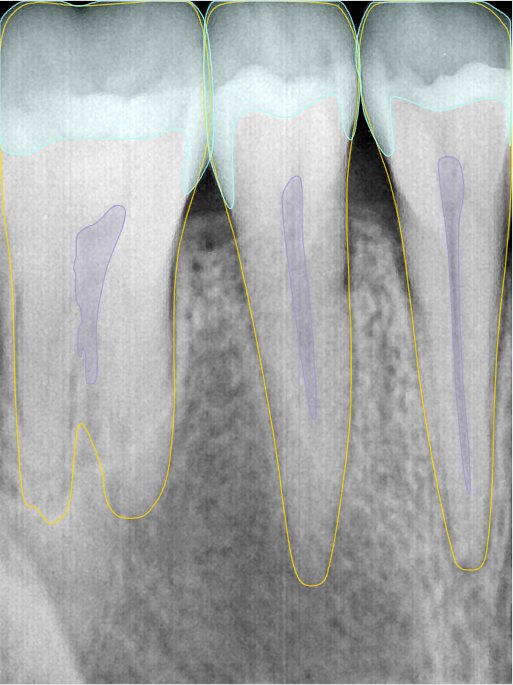

第二版算法问题测试

| 第一版 | 第二版 | 是否解决 | |

|---|---|---|---|

![]() | ![]() ![]() 边角识别有问题 龋齿识别不全 牙髓识别不全 | ![]() | 解决 |

![]() | ![]() 边角识别有问题 识别信息有误 自查(牙冠识别不全) | ![]() | 解决 |

![]() | ![]() ![]() 边角识别有误 大范围填充识别遗漏 | ![]() | 解决 |

![]() | ![]() 识别信息不全 | ![]() | 解决 |

![]() | ![]() ![]() 边角问题 牙胶识别不全 牙冠识别不全 | ![]() | 解决 |

![]() 换图片 | ![]() | ![]() 牙冠部分稍微白了一些就识别成小范围修补,部分判断异常 | 部分解决,修复类略敏感,牙冠部分稍微白了一些就识别成小范围修补,部分判断异常。 |

![]() | ![]() ![]() 牙冠识别不全 牙髓不全 根尖炎龋齿识别有误 | ![]() | 解决 |

![]() | ![]() | ![]() | 解决 |

![]() 换图片 | ![]() | ![]() | 解决 |

![]() | ![]() 牙冠识别有误 | ![]() | 解决 |

![]() 换图片 | ![]() ![]() 边角识别有误 | ![]() 修复类敏感 | 部分解决,图像过白,导致修复类判断异常。 |

![]() 换图片 | ![]() 牙冠识别不全 | ![]() 修复类敏感 | 部分解决,图像过白,导致修复类判断异常 |

结论:修复类出现了不鲁棒的情况,后续需要加入轮廓的扩充数据进行增强。